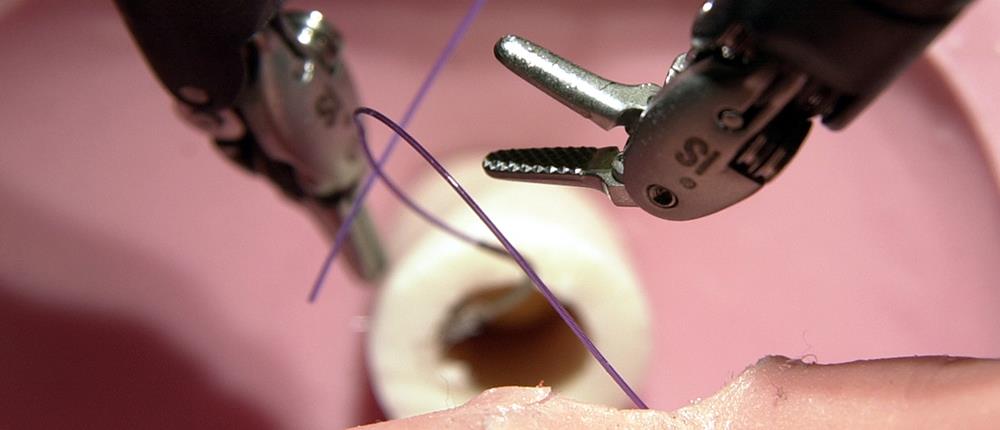

Τα τελευταία χρόνια η εξέλιξη στη Χειρουργική των κηλών του κοιλιακού τοιχώματος με τη χρήση Ρομποτικών συστημάτων είναι αλματώδης. Από το 1990 όπου και πρωτοπαρουσιάστηκε η Λαπαροσκοπική Χειρουργική, μέχρι και το 2016, δηλαδή για περισσότερο από 25 χρόνια, οι διαθέσιμες τεχνικές για την επιδιόρθωση μιας κήλης ήταν ελάχιστες και πάντα οι ίδιες, χωρίς καμία νεότερη και εξελιγμένη χειρουργική μέθοδο.

Η έλευση των ρομποτικών μηχανημάτων και η ολοένα και πιο ευρεία χρήση τους σε ολόκληρο τον κόσμο αφενός, και η ανάπτυξη νέων τεχνικών από 2-3 φωτισμένους Αμερικανούς χειρουργούς αφετέρου, έφεραν και στην Ελλάδα από το 2018 τις πλέον προηγμένες τεχνικές για την αποκατάσταση κοιλιοκηλών και μετεγχειρητικών κηλών. Πρόκειται για τις ρομποτικές επεμβάσεις οπισθίου διαχωρισμού του κοιλιακού τοιχώματος, ή πιο σύντομα επεμβάσεις eTEP (enhanced Total Extra Peritoneal), RS (Rives - Stoppa) και TAR (Transversus Abdominis Release). Πρώτος στην Ελλάδα τότε, ο δρ Φώτης Αρχοντοβασίλης, Διευθυντής της ΣΤ’ Χειρουργικής Κλινικής του θεραπευτηρίου Metropolitan General, εφάρμοσε με απόλυτη επιτυχία την πρώτη Ρομποτική eTEP-TAR σε ασθενή με πολλαπλές υποτροπές μετεγχειρητικής κοιλιοκήλης.

Μέσα σε αυτά τα 6 σχεδόν χρόνια, η ομάδα του κ. Αρχοντοβασίλη πραγματοποίησε εκατοντάδες Ρομποτικές αλλά και Λαπαροσκοπικές επεμβάσεις με τις τεχνικές eTEP, eTEP-RS και eTEP-TAR, με όλο και μεγαλύτερο βαθμό δυσκολίας, και πάντα με συνεχή εκπαίδευση στα μεγαλύτερα κέντρα του κόσμου.

Τον Ιούνιο του 2024, ο δρ Αρχοντοβασίλης πραγματοποίησε για πρώτη φορά στην Ελλάδα μια από τις πιο σύνθετες επεμβάσεις Ρομποτικής αποκατάστασης κηλών του κοιλιακού τοιχώματος. Επρόκειτο για πολυχειρουργημένο ασθενή, με πολλαπλές υποτροπές κηλών στο κοιλιακό του τοίχωμα (μετά από παλαιότερες επεμβάσεις), ο οποίος έπασχε από δύο ευμεγέθεις μετεγχειρητικές κοιλιοκήλες, διάσταση της λευκής γραμμής, κήλη Spigel, και βουβωνοκήλη. Δηλαδή παρουσίαζε σχεδόν το σύνολο των κηλών που μπορεί να παρουσιαστούν σε έναν άνθρωπο.

Τον Ιούνιο του 2024, ο δρ Αρχοντοβασίλης πραγματοποίησε για πρώτη φορά στην Ελλάδα μια από τις πιο σύνθετες επεμβάσεις Ρομποτικής αποκατάστασης κηλών του κοιλιακού τοιχώματος. Επρόκειτο για πολυχειρουργημένο ασθενή, με πολλαπλές υποτροπές κηλών στο κοιλιακό του τοίχωμα (μετά από παλαιότερες επεμβάσεις), ο οποίος έπασχε από δύο ευμεγέθεις μετεγχειρητικές κοιλιοκήλες, διάσταση της λευκής γραμμής, κήλη Spigel, και βουβωνοκήλη. Δηλαδή παρουσίαζε σχεδόν το σύνολο των κηλών που μπορεί να παρουσιαστούν σε έναν άνθρωπο.

Με τη χρήση του ρομποτικού συστήματος Da Vinci Xi, και μέσω μόνο πέντε οπών των 8 χιλιοστών, αποκαταστάθηκαν ταυτόχρονα και οι τέσσερις κήλες αλλά και η διάσταση. Το πλέον ενδιαφέρον όμως ήταν ότι χρησιμοποιήθηκε για πρώτη φορά η τεχνική eTEP με Περιτοναϊκό Κρημνό (peritoneal flap), χωρίς να χρειαστεί να γίνει διατομή των εγκαρσίων κοιλιακών μυών (μέθοδος TAR). Πρόκειται για μια ιδιαίτερα δύσκολη τεχνική που όμως δίνει εξαιρετικά αποτελέσματα, όταν διενεργείται από άκρως εξειδικευμένους χειρουργούς κηλών.

Όλη η επέμβαση έγινε εξωπεριτοναϊκά, χωρίς να χρειαστεί να μπει καθόλου μέσα στη κοιλιά ο χειρουργός. Πραγματοποιήθηκε ανάμεσα στα μυϊκά διαμερίσματα του ασθενούς και τα πλέγματα που χρησιμοποιήθηκαν τοποθετήθηκαν εκτός της κοιλίας με πλήρη κάλυψή τους από το περιτόναιο, χωρίς να έρχονται σε καμία επαφή με τα ενδοκοιλιακά σπλάγχνα.

Η μετεγχειρητική πορεία του ασθενούς ήταν άριστη και εξήλθε από το νοσοκομείο σε λιγότερο από 48 ώρες.